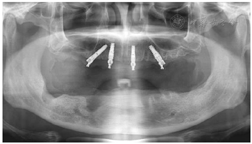

(2)2015年9月行拔牙及上颌种植手术。口腔局部阿替卡因肾上腺素注射液浸润麻醉,拔除上下颌余留牙,搔刮清理拔牙窝内肉芽组织,见43、44、47区牙槽骨缺损(图4),修整下颌牙槽嵴,黏膜瓣复位,4-0可吸收缝线缝合下颌术区。16~26区牙槽嵴顶近远中向切开牙龈黏膜、翻瓣,平整牙槽嵴顶骨嵴,分别于12、15、22、25区定点,逐级备洞,15区倾斜植入Nobel Speedy 4 mm×15 mm种植体,12、22、25区骨质量较差,为获得良好初期稳定性选用Nobel Active种植体,12区植入Nobel Active 5 mm×13 mm种植体,22区植入Nobel Active 4.3 mm×13.0 mm种植体,25区倾斜植入Nobel Active 5 mm×13 mm种植体,种植体初期稳定性均达到35 N·cm,旋入复合基台,修整牙龈,缝合。术后拍摄全颌曲面体层片(图5)。